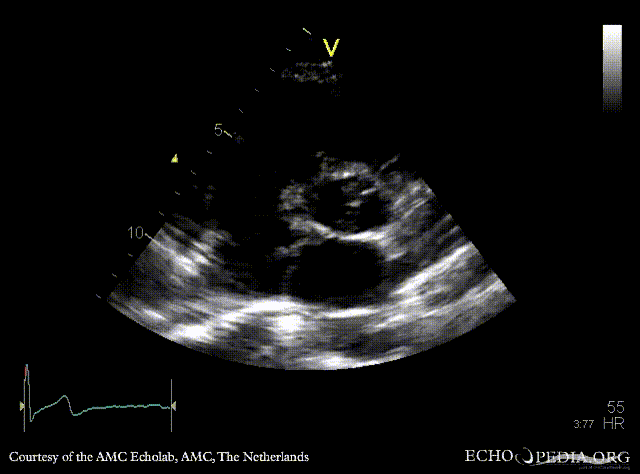

PSAX: Eustachian valve in right atrium, left coronary artery a vue PSAX: right coronary artery a vue